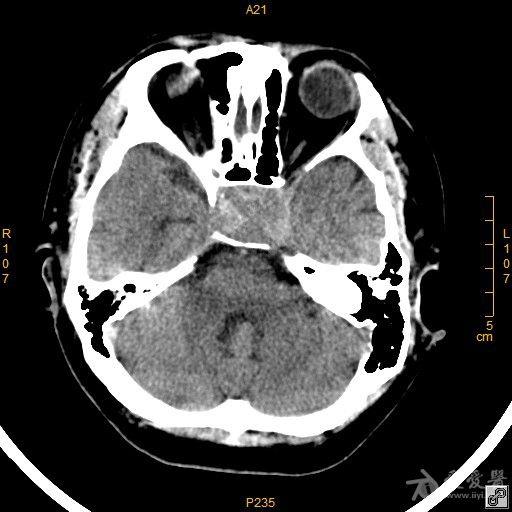

病例42 鞍区脑膜瘤一例

鞍区肿瘤,女,49岁